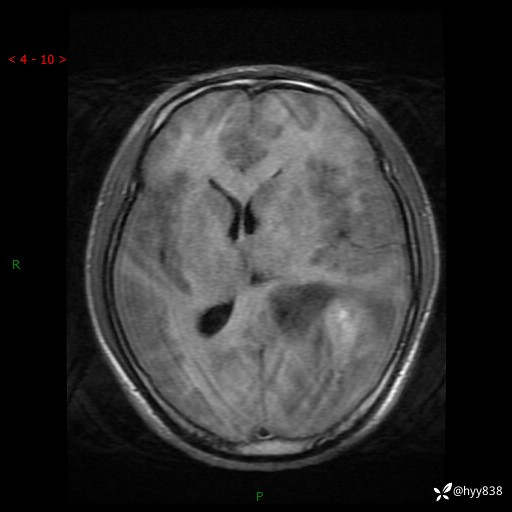

病例年轻小伙,头痛伴呕吐半年,渐进性加重1月。疑难病例,第一次见--结果公布~

性别:男

年龄:21岁

简要病史:头痛伴呕吐半年,渐进性加重1月

颅脑MRI平扫+增强